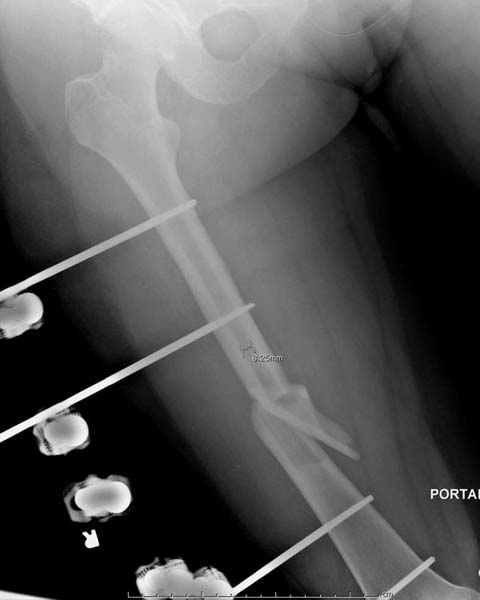

> Остеосинтез бедра не стали делать из-за множественных переломов ребер с

> ушибом грудной клетки и поэтом у закончили фиксацию бедра наружным

> фиксатором.

> Около 11.00 вечера больная переведена в реанимацию, без сознания, но

> стабильная.. На третьий день провели стабилизацию перелома бедра

> антеградным остеосинтезом.